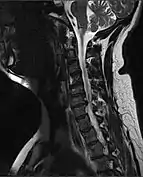

MRI of fractured and dislocated neck vertebra that is compressing the spinal cord

X-rays (left) are more available, but can miss details like herniated disks that MRIs can show (right).[85]

A radiographic evaluation using an X-ray, CT scan, or MRI can determine if there is damage to the spinal column and where it is located.[9] X-rays are commonly available[85] and can detect instability or misalignment of the spinal column, but do not give very detailed images and can miss injuries to the spinal cord or displacement of ligaments or disks that do not have accompanying spinal column damage.[9] Thus when X-ray findings are normal but SCI is still suspected due to pain or SCI symptoms, CT or MRI scans are used.[85] CT gives greater detail than X-rays, but exposes the patient to more radiation,[87] and it still does not give images of the spinal cord or ligaments; MRI shows body structures in the greatest detail.[9] Thus it is the standard for anyone who has neurological deficits found in SCI or is thought to have an unstable spinal column injury.[88]